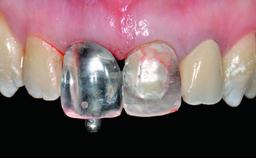

Abutment Type CAD/CAM

Prosthesis Type FDP

Loading Protocol Conventional or early

Retention Screw-retained Screw-retained